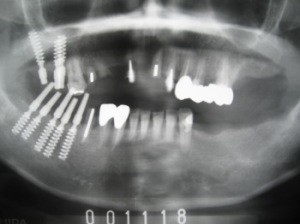

| 2000年11月18日に右の上下にインプラント植立。 同時に金属製の前歯を除去して、右奥歯と前歯にプラスチック製の歯(仮歯)を作る。 |